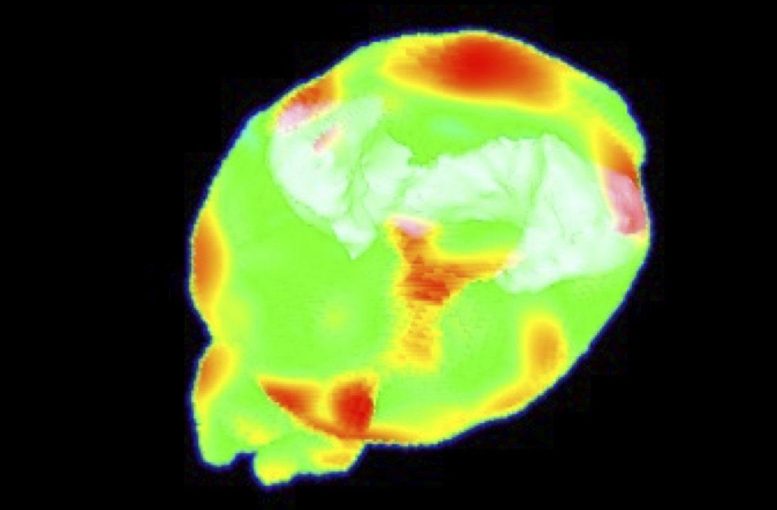

APOE4靶替代小鼠模型注射放射性花生四烯酸示踪剂的PET图像,由Kai Chen博士开发。红色区域显示花生四烯酸,一种脂肪酸。这项技术用于研究APOE4如何影响脑脂质和炎症。